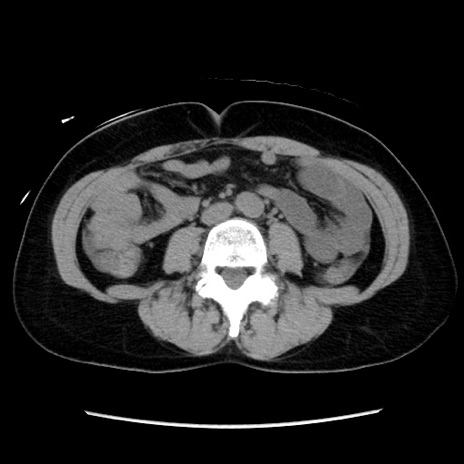

症例10(横断像)

【症例】 50歳代女性

【主訴】 腹痛

【現病歴】前日生レバーを食べた。今朝に排便あり。 昼前に突然発症の腹痛を生じ、当院救急外来を受診した。

【身体所見】 意識清明、腹部:平坦、軟、下腹部やや左を中心に圧痛・反跳痛あり、筋性防御あり